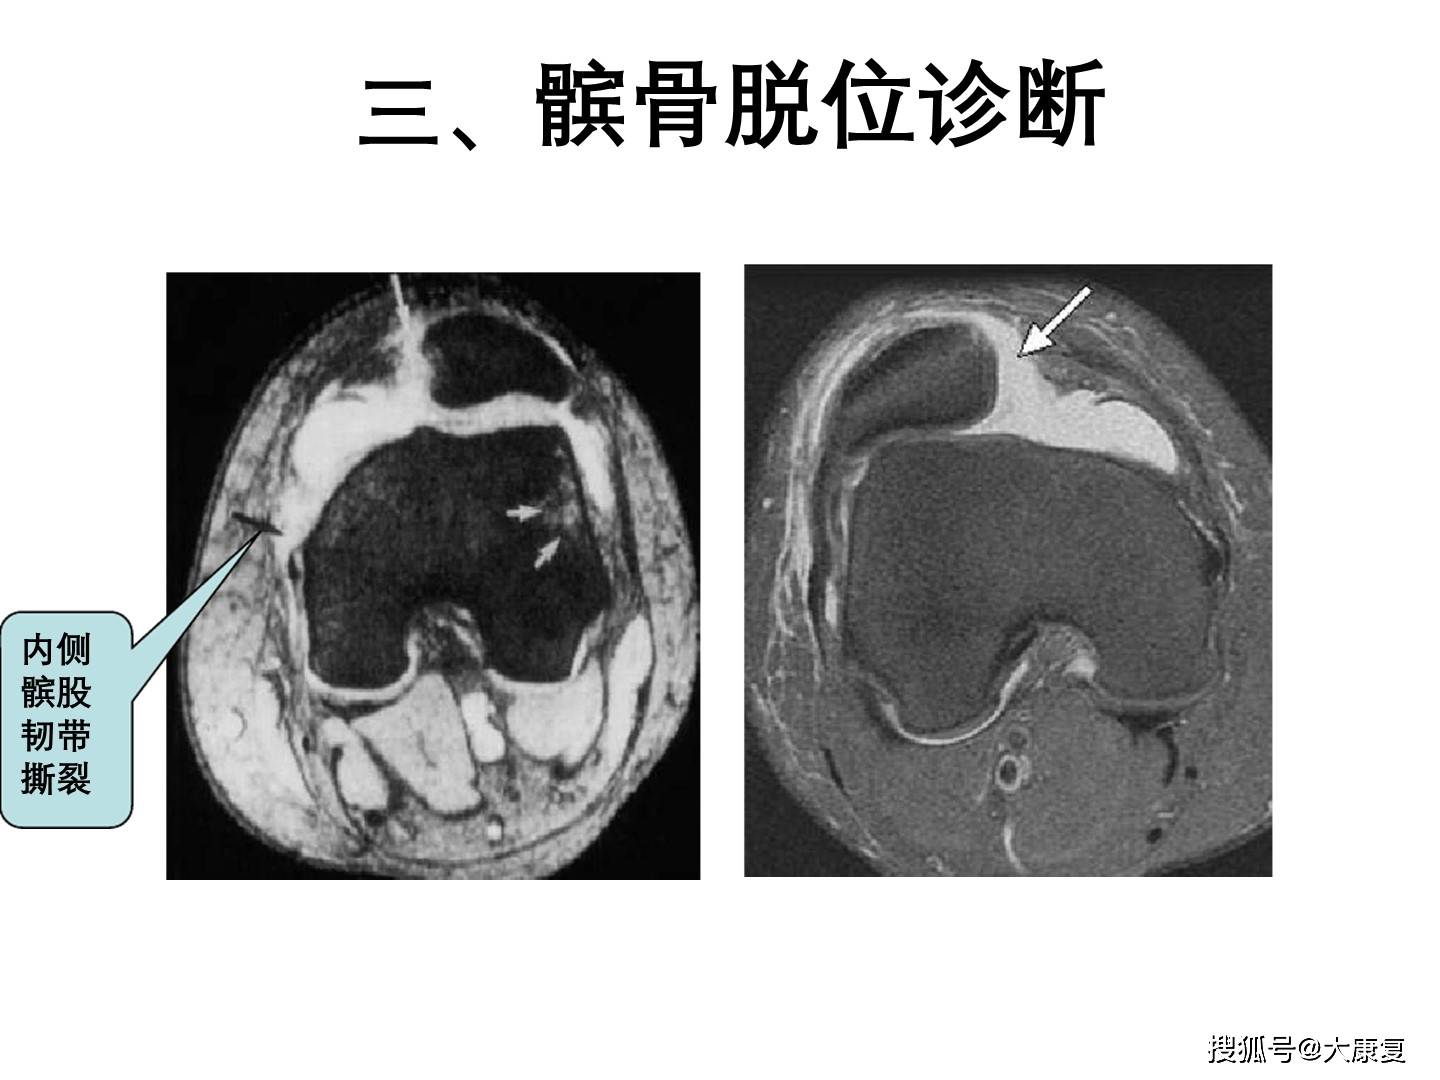

医学影像复发性髌骨脱位ppt